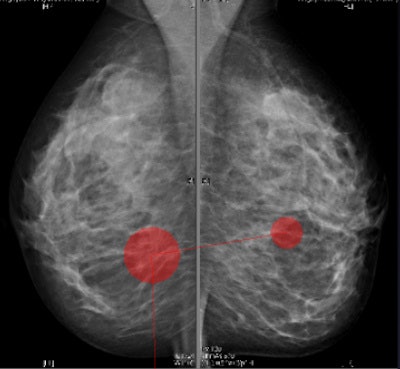

In a study presented at last month's ECR 2016, the Dublin team sought to determine not only radiologists' behavior when interpreting mammographic images, but also whether breast density plays a role in fixation time. Breast radiologists from the U.K. were voluntarily recruited to review sets of anonymized mammographic images (n = 170) and to subjectively rate the breast density according to the BI-RADS categorization.

The researchers obtained data obtained for 17 radiologists, who reviewed the mammography images using standardized viewing conditions and Ziltron software. Results showed the radiologists spent significantly more time observing MLO (MLO: 1.67 sec. versus CC: 1.32 sec.) and right images (right: 1.63 sec. versus left: 1.36 sec.). They also spend significantly more time observing images with BI-RAD 3 (mean = 1.48 sec.) density than the other BI-RADS categories.